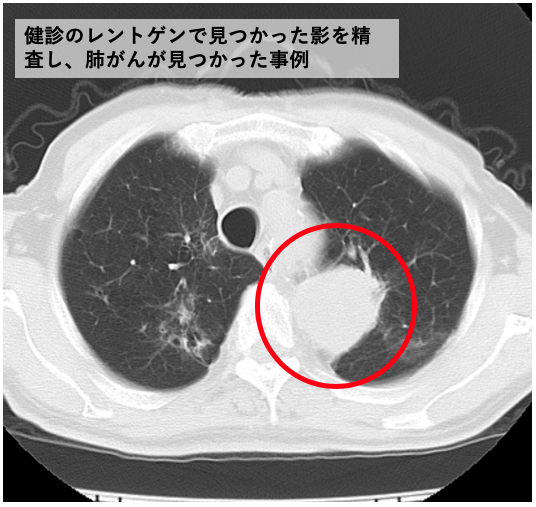

胸部のCT 第4版 | 村田喜代史, 上甲 剛, 村山貞之, 酒井文和 |本。胸部のCT 第4版 | 村田喜代史, 上甲 剛, 村山貞之, 酒井文和 |本。CC3 胸部CTの読影 - YouTube。kokuu 雑穀米 ホワイトブレンド グルテンフリー 2袋。CANON社製新型CT装置を導入 | 新柴又駅前クリニック(脳神経外科)。腹部CTを読影する上で重要な脂肪ウインドウとは? - YouTube。胸部CTの読影の基礎【働くのに必要な知識を最短で習得する方法。胸部CT画像の読影を支援するEIRL Chest CTの販売を開始 - エル。見逃しを防ぐための腹部CTの読影の順番|ごろ〜にゃ@放射線科医。18203920 | 腹部CT CBT | M3E Medical。体幹部領域-Aquilion PRIMEの各領域における技術 - 東芝。CT¹⁾検査|検査ガイド|患者さん向けガイド|原三信病院。腹部CT検査 胆石 - 医療のイラスト・写真・動画、素材販売サイト。胸部と腹部のCTに関する専門書、最新の知見を網羅。- 書籍名: 胸部のCT 第4版- 書籍名: 腹部のCT 第3版- 出版社: MEDSi- 書籍の状態: 良好- ISBN: 9784895921877- ISBN: 9784895921860ご覧いただきありがとうございます。○バラ売り希望にも対応します。(価格は応相談)コメントください!○未使用ですが、自宅保存のため運搬による傷が少しあります。○未使用のためメモなどはありません。カバーも目立った傷はありません。○できるだけ早く発送します。お急ぎの方はコメントください。